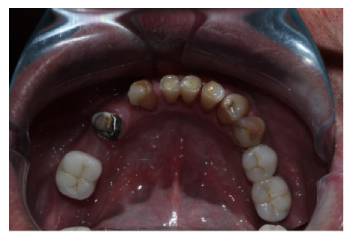

• The upper arch was restored using a digitally milled titanium iBAR framework. It was topped with Illusion Zirconia Dental Bridge. This provided them with an extremely precise fit and long-term stability. (Fig: 3.1, 3.2)

Occlusal view of maxillary implant fixtures (Fig 3.1) and the completed iBAR-supported Illusion Zirconia prosthesis (Fig 3.2).